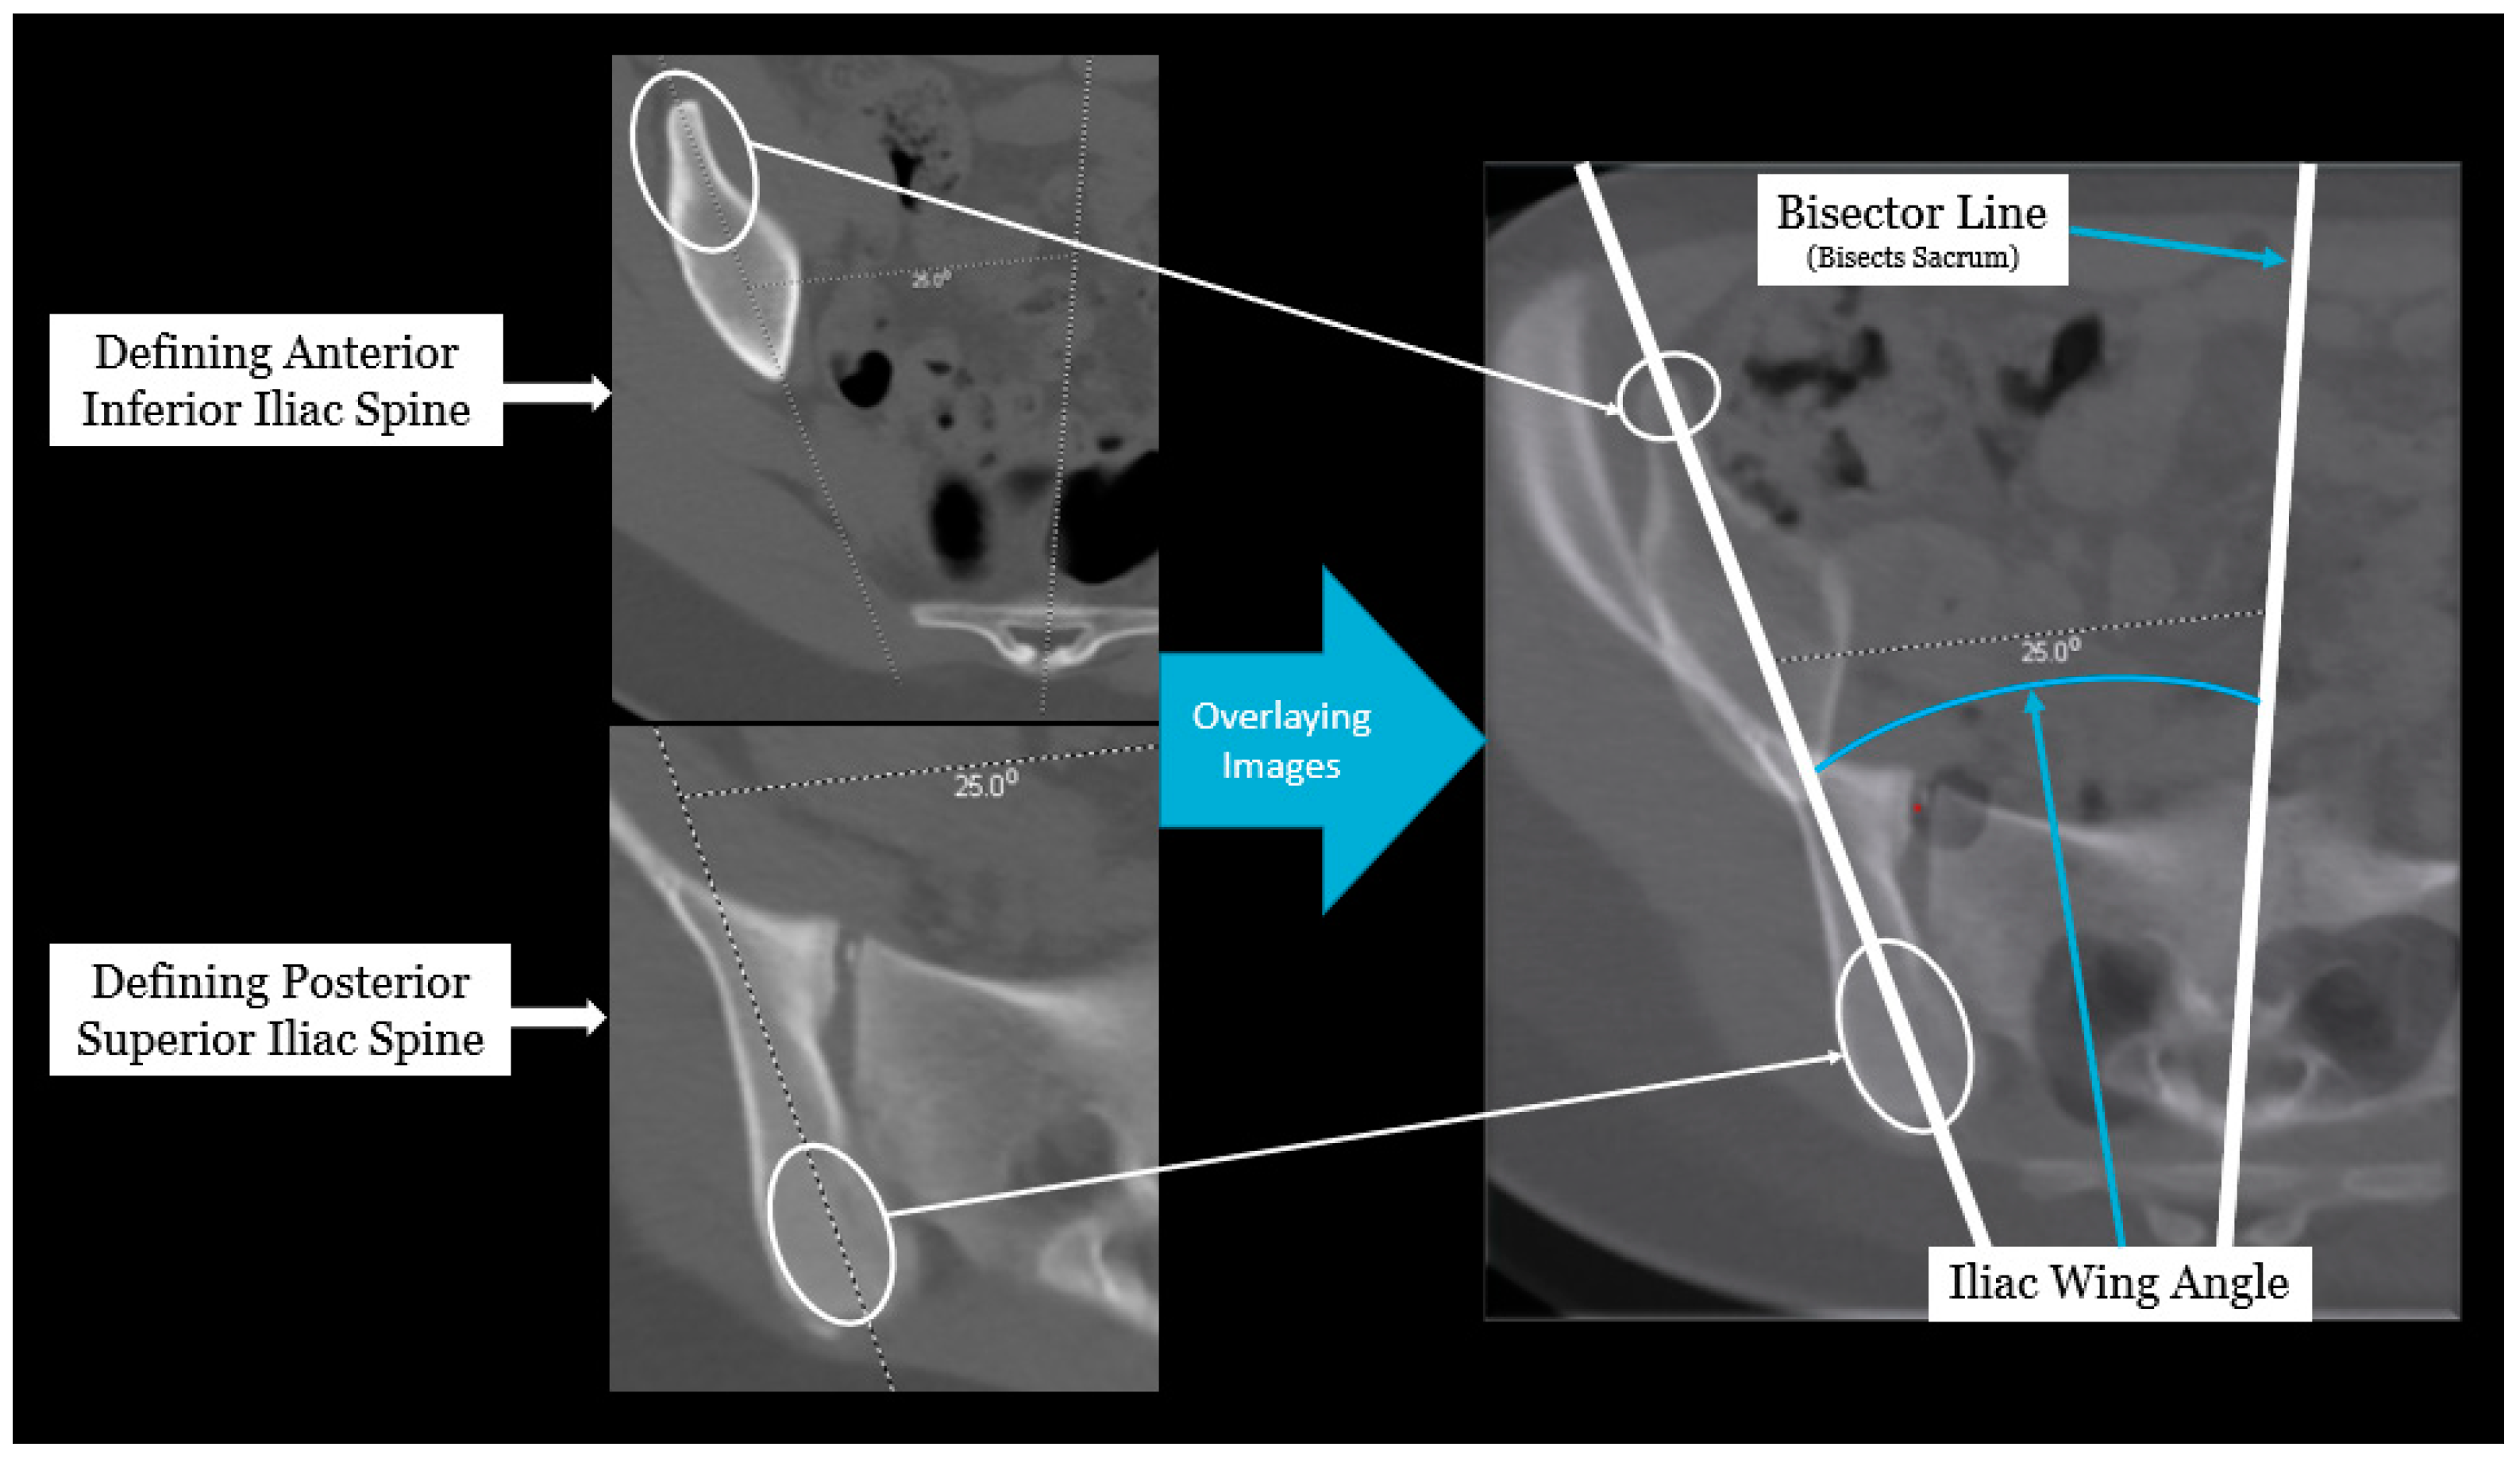

Axial pelvic asymmetry was evaluated with respect to the supra-acetabular region of bone using two landmarks for the iliac wing and sacral ala each. We identified two landmarks for iliac wing which utilized the supraacetabular osseous corridor connecting the anterior inferior iliac spine and the posterior superior iliac spine. For the sacral ala, the highest points of the medial and lateral peak of each hemi-sacrum were used. We used the highest points of the sacral ala as these may represent the rotational change brought about by the imbalance of muscular forces that may produce uneven medial and lateral peaks for each hemi-sacrum. The deformity was measured using two angles—the iliac wing angle and the sacral ala angle. The aforementioned landmarks for the iliac wing and sacral ala were checked for consistency in each axial slice to best represent them as fixed points in each hemipelvis. This was performed to eliminate or minimize the effects of sagittal and coronal plane obliquity using the “copy to all” function on ISITE (Phillips Imaging Inc.). First, we measured the angle between a line bisecting the sacrum and a line drawn from the midportion of the posterior ilium to the midportion of the anterior inferior iliac spine (ASIS) referred to as the iliac wing angle to assess the iliac wing asymmetry (Figure 1). A second angle was measured between a line across the highest points of the sacral ala and the sacral bisector to assess the sacral ala asymmetry, termed the sacral ala angle (Figure 2). The larger of the two angles was considered externally rotated while the smaller angle was considered internally rotated. For each hemipelvis, external/internal rotation (ER/IR) of the iliac wing and sacral ala were termed iliac wing external (IWE)/iliac wing internal (IWI) and sacral ala external (SAE)/sacral ala internal (SAI) respectively. Absolute differences in ER/IR of the iliac wing and sacral ala for one hemipelvis with the corresponding contralateral hemipelvis of the same subject were termed as iliac wing angle difference and sacral ala angle difference, respectively. Additionally, if the patients with cerebral palsy and neuromuscular scoliosis had a full spine AP radiograph available for the measurement of Cobb’s angle (taken prior to any spinal instrumentation), it was recorded. All radiological measurements were reviewed by two authors (A.N.S and J.Z) of this study. To determine inter-observer reliability, two authors reviewed all the angles and were blinded to each other’s measurements. The first author’s measurements were used for analysis.

Figure 1. Radiographic measurement technique for iliac wing angle.